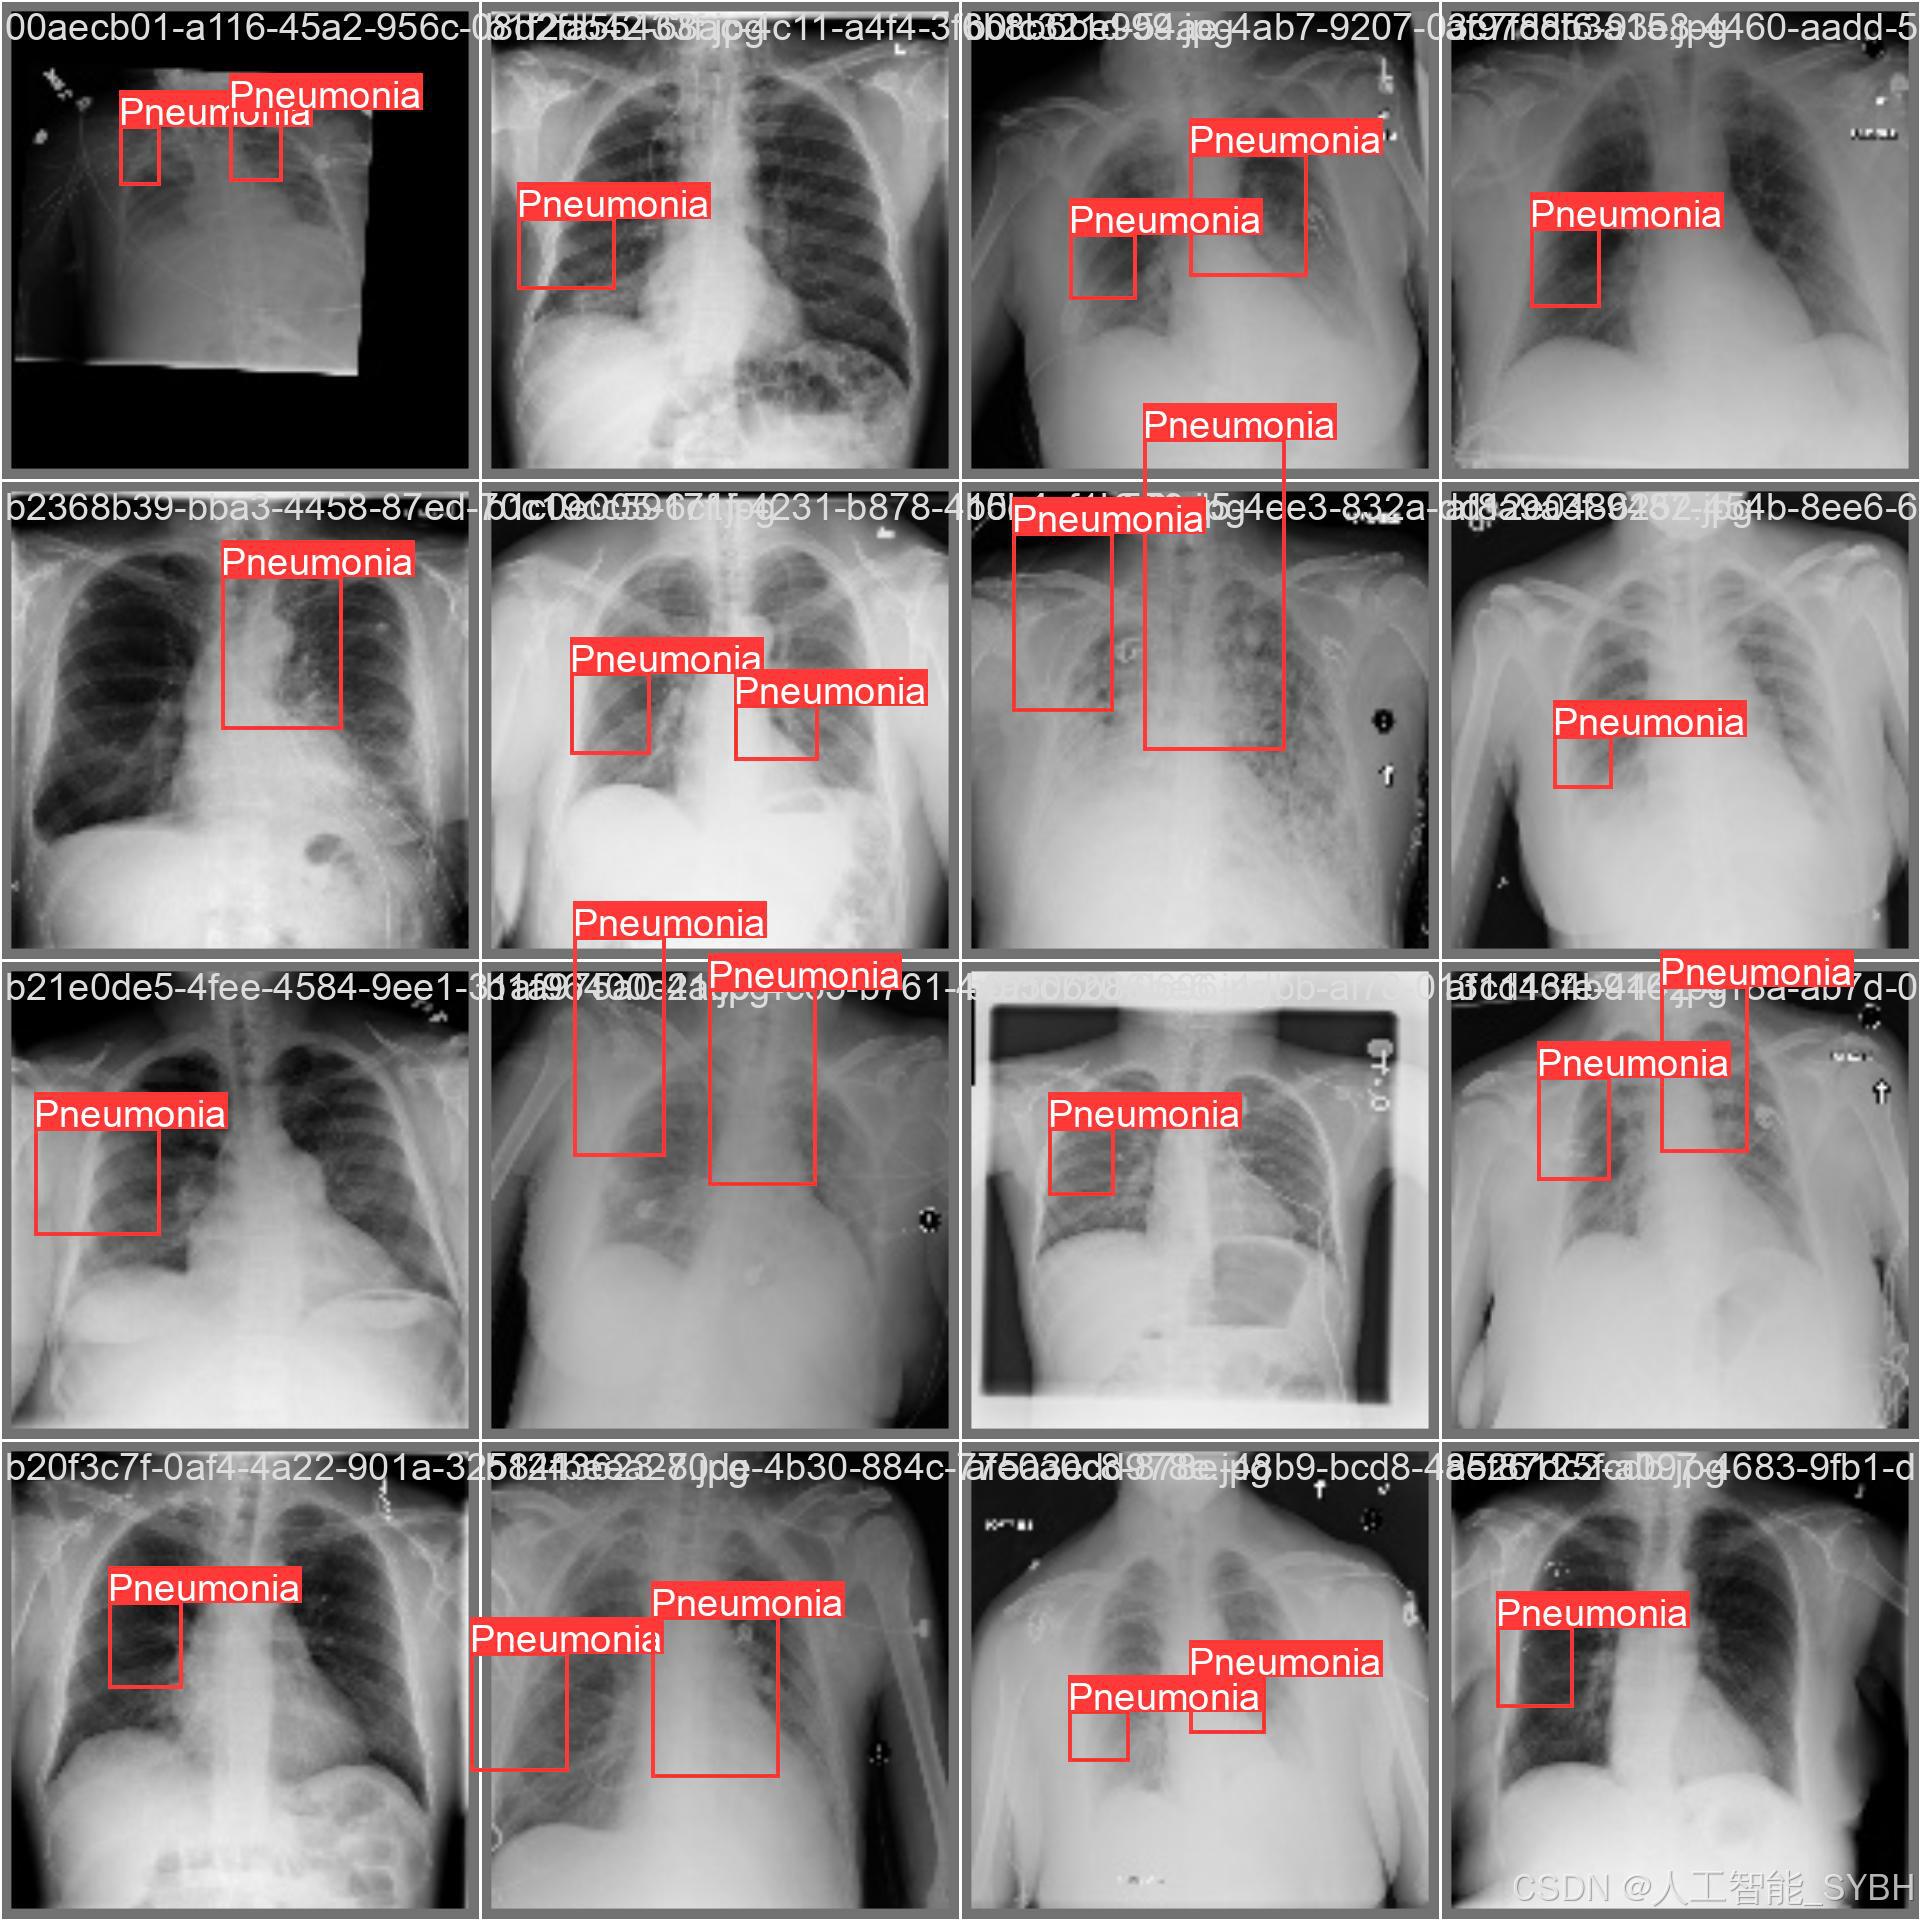

三、数据集介绍

数据集名称: 肺炎检测数据集

数据集内容:

-

类别数量 (nc): 1类

-

类别名称: ['Pneumonia']

-

Pneumonia: 肺炎

-

-

-

数据集规模:

-

训练集: 3772张图像

-

验证集: 539张图像

-

测试集: 1078张图像

-

数据来源:

-

数据集通过收集医院中的胸部X光片构建,涵盖了不同年龄段、性别和病情的患者,以确保模型的泛化能力。

数据标注:

-

每张图像中的肺炎区域均使用边界框(Bounding Box)标注,并标注对应的类别。

-

标注格式为YOLO格式(class_id, x_center, y_center, width, height),便于直接用于YOLOv8模型的训练。

数据增强:

-

为提高模型的鲁棒性,数据集进行了以下增强处理:

-

随机旋转

-

亮度调整

-

对比度调整

-

水平翻转

-

添加噪声

-

数据集特点:

-

多样性: 数据集包含不同患者的胸部X光片,覆盖了多种病情和拍摄条件。

-

高质量: 图像分辨率高,标注精确,适合深度学习模型的训练。

-

平衡性: 数据集经过合理划分,确保模型在训练过程中能够充分学习特征,并在验证集和测试集上表现出良好的泛化能力。